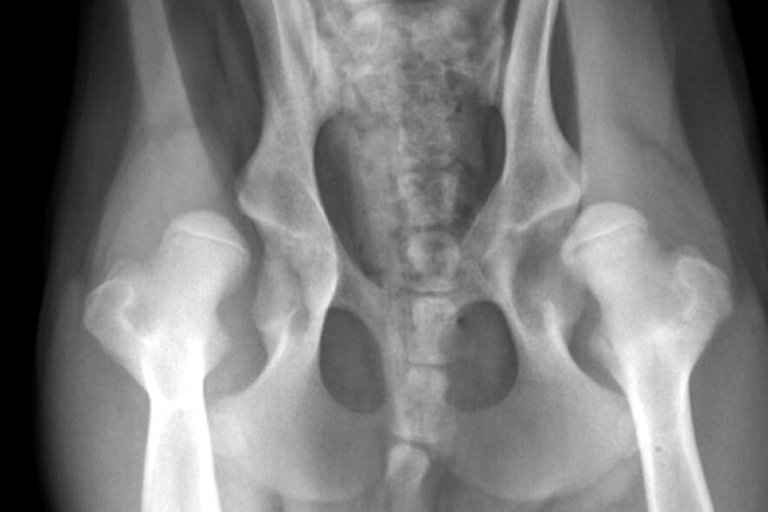

La displasia de cadera: qué es y cómo detectarla.

La displasia de cadera es una patología ortopédica hereditaria de evolución lenta que se caracteriza por…